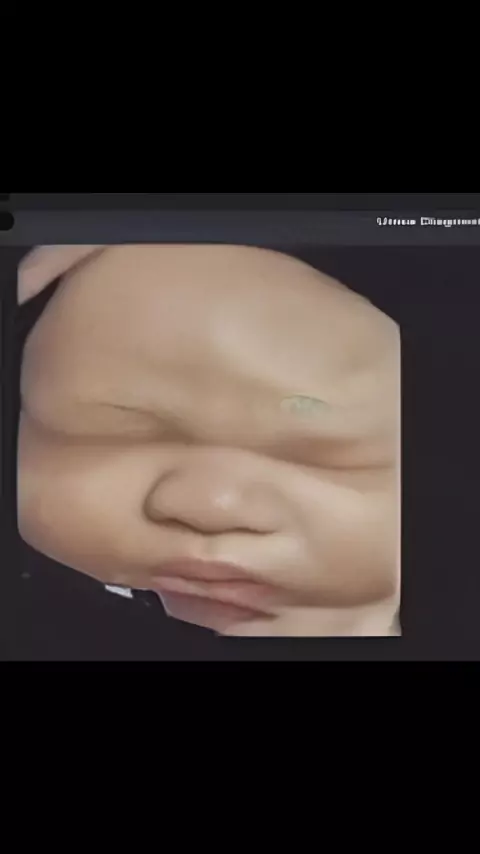

ultrassom 4D obstetrico.